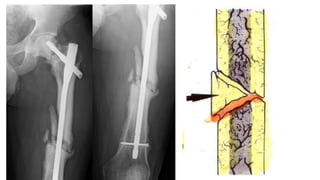

DATOS RADIOGRAFICOS

Persistencia de la línea

fracturaría e incluso

ensanchamiento de la misma

más allá del tiempo

considerado como normal

para la consolidación.

Falta de progresión del callo o

la persistencia de la misma

imagen fracturaría a lo largo

de 3 controles radiográficos

mensuales consecutivos.

TRATAMIENTO

 Hipervasculares:

 Reducción abierta

 Fijación segura con placas de compresión dinámica y tornillos o con

clavo endomedular bloqueado

 Avasculares:

 Reducción quirúrgico.

 Fijación segura con placa y tornillos o clavo endomedular bloqueado

 Colocación de injerto óseo de tipo esponjoso.